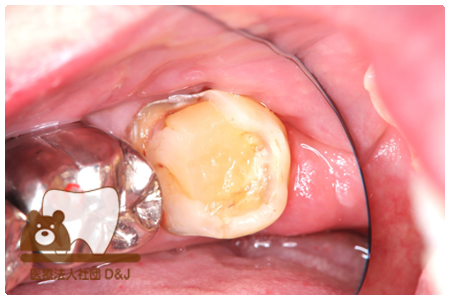

症例3フリジルコニアクラウン 左上6

治療前

治療後

59歳 男性

- 治療内容

- 虫歯で大きく失われた歯に対して、土台としてファイバーコアを使用し、その上にフルジルコニア製の被せ物を装着しました。見た目と強度を両立した自由診療の治療です。

- 治療期間

- 根の治療含めて3カ月半

- 費用

- 自費

フリジルコニアクラウン:77,000円(税込)

(R8.2月時点)

- その他の治療の費用は含まれておりません。

- リスク・副作用

- 強い力が加わると割れる可能性があります。また、噛み合わせや歯ぎしりの影響で脱離することがあります。